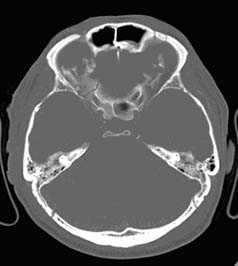

Компьютерная томография является очень важной методикой в оценке травмы головы, и относится к методам первого выбора. Исследование проводится очень быстро (менее одной минуты). КТ высоко чувствительна к крови и хороша для изучения костей, воздуха (пневмоцефалии) и рентгенологически плотных инородных тел. Для обеспечения максимальных диагностических возможностей томограммы при черепно-мозговой травме должны быть рассмотрены в разных режимах для выявления первых признаков инсульта, оценки паренхимы, крови и кости/воздуха/жира.

а) Признаки перелома черепа на КТ и МРТ. С помощью компьютерной томографии можно диагностировать три типа перелома черепа: линейные, вдавленные и диастатические. Для визуализации линейных переломов и малых трещин используются алгоритмы реконструкции и фильтры. Переломы черепа могут сопровождаться сопутствующей внутричерепными измененями: гематомами, ушибами, пневмоцефалией или наличием инородных тел, которые могут быть так же выявлены с помощью КТ. Если при переломе имеются раны мягких тканей покровов черепа, то он называется «открытым», так как возникает потенциальная связь между внутричерепным пространством и окружающей средой. В противном случае он называется «закрытым».

- В остальных случаях на нормальных КТ-срезах возможно появление воздуха внутри черепа (пневмоцефалия) или отсутствие воздуха в обычных областях, например, в околоносовых пазухах, сосцевидных ячейках, среднем ухе или наружном слуховом проходе.

- При отсутствии патологических изменений до травмы возможно жидкостное заполнение пространства СМЖ или кровью, менее плотной по сравнению с СМЖ (метод внутреннего жидкостного наполнения).